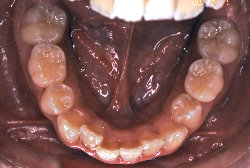

「ものがうまく噛めない」という主訴で来院したケースです。診断の結果、「骨格性反対咬合に伴う咬合不良+軽度叢生」と判明しました。原因としては特に下顎の左側が過成長したため、骨格性反対咬合になり、特に左側での噛み合わせが非常に悪くなっていると診断しました。初診時の写真を見ると、上下の正中線の大きなズレ、左側の噛み合わせの不良がはっきり分かります(黄色の矢印と緑の矢印は一致しているのが正しい状態です)。